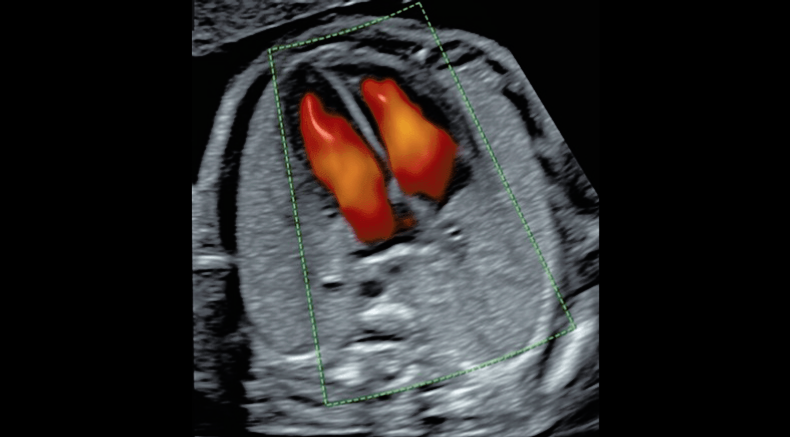

3D/4D rendering of intracardiac flow using spatiotemporal image correlation (STIC)

Chaoui, R. (2021), Evolution of fetal cardiac imaging in 30 years of ISUOG. Ultrasound Obstet Gynecol, 57: 38-42. https://doi.org/10.1002/uog.23551